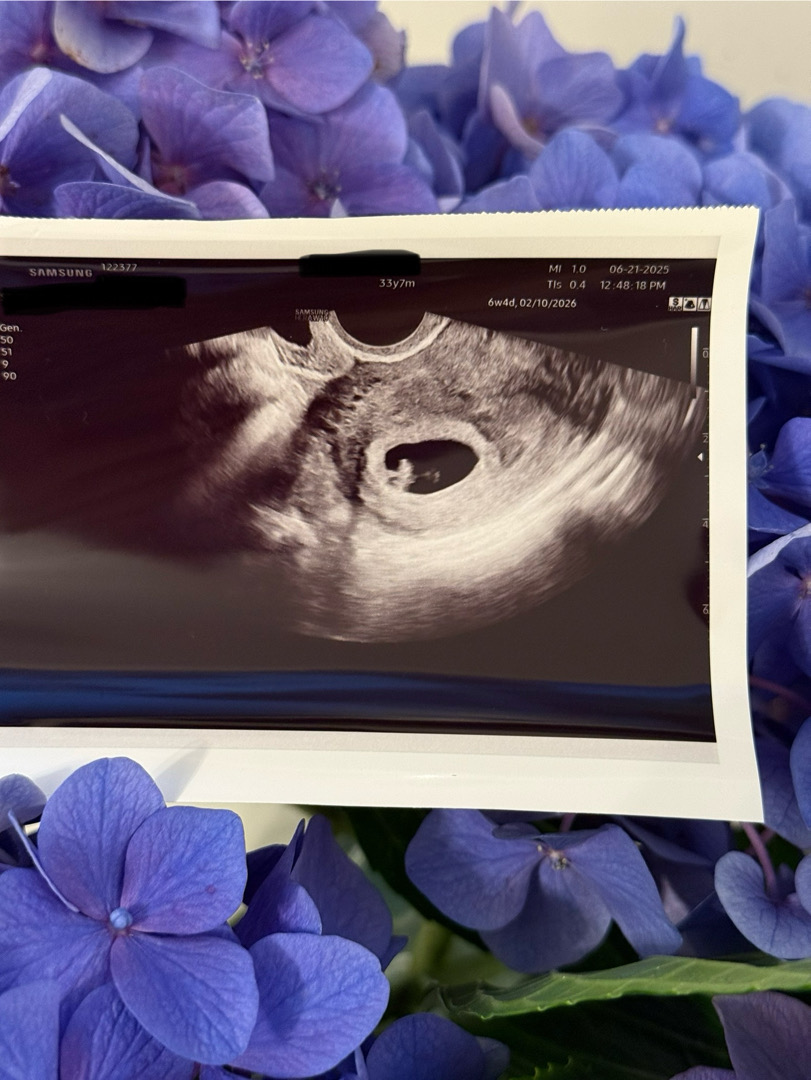

6주5일차 애기심장소리 듣고왔어요!!🩷

안녕하세요, 저는 6주5일차 오복이 엄마 입니다. 오늘 임테기 확인 후 첫 산부인과 진료가 있었고, 초음파 확인 및 애기심장 소리를 들었습니다. 아직 0.7cm 라고 너무 작은 콩 사이즈 만한 애기인데, 어떻게 심장 소리가 그렇게 크게 나는지 너무 신기했어요 ㅎㅎ 제가 현재 미국에서 거주 중이고 부모님도 옆에 안 계신 와중에 남편과 둘이 첫 임신이라, 사실 임신 자체가 많이 새롭고 어색하기만 한데, 그래도 오복이 만날때 까지 최선을 다해 열심히 해볼 생각입니다 ㅎㅎ 다른 임산부 분들께서도 더운 여름 함께 화이팅 해요!! 🩷 모두 축하드립니다